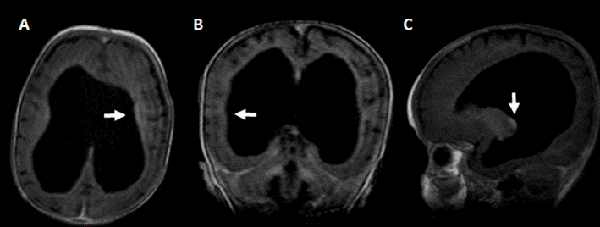

Actualmente tras 14 meses de seguimiento, la paciente se encuentra asintomática y en el control de resonancia magnética realizada a los 12 meses de post quirúrgico donde se observó disminución del tamaño ventricular ausencia de tabiques interventriculares, y ausencia de realce tras la administración de contraste (Figura 2).

Figura 2: RM de encéfalo realizada a los 12 meses post quirúrgico de la colocación de la DVP: A) corte axial, B) coronal, C) sagital, ponderado en T1 con contraste. Se observa disminución del tamaño ventricular en comparación con resonancia previa, sin realce ependimario tras la administración de contraste.